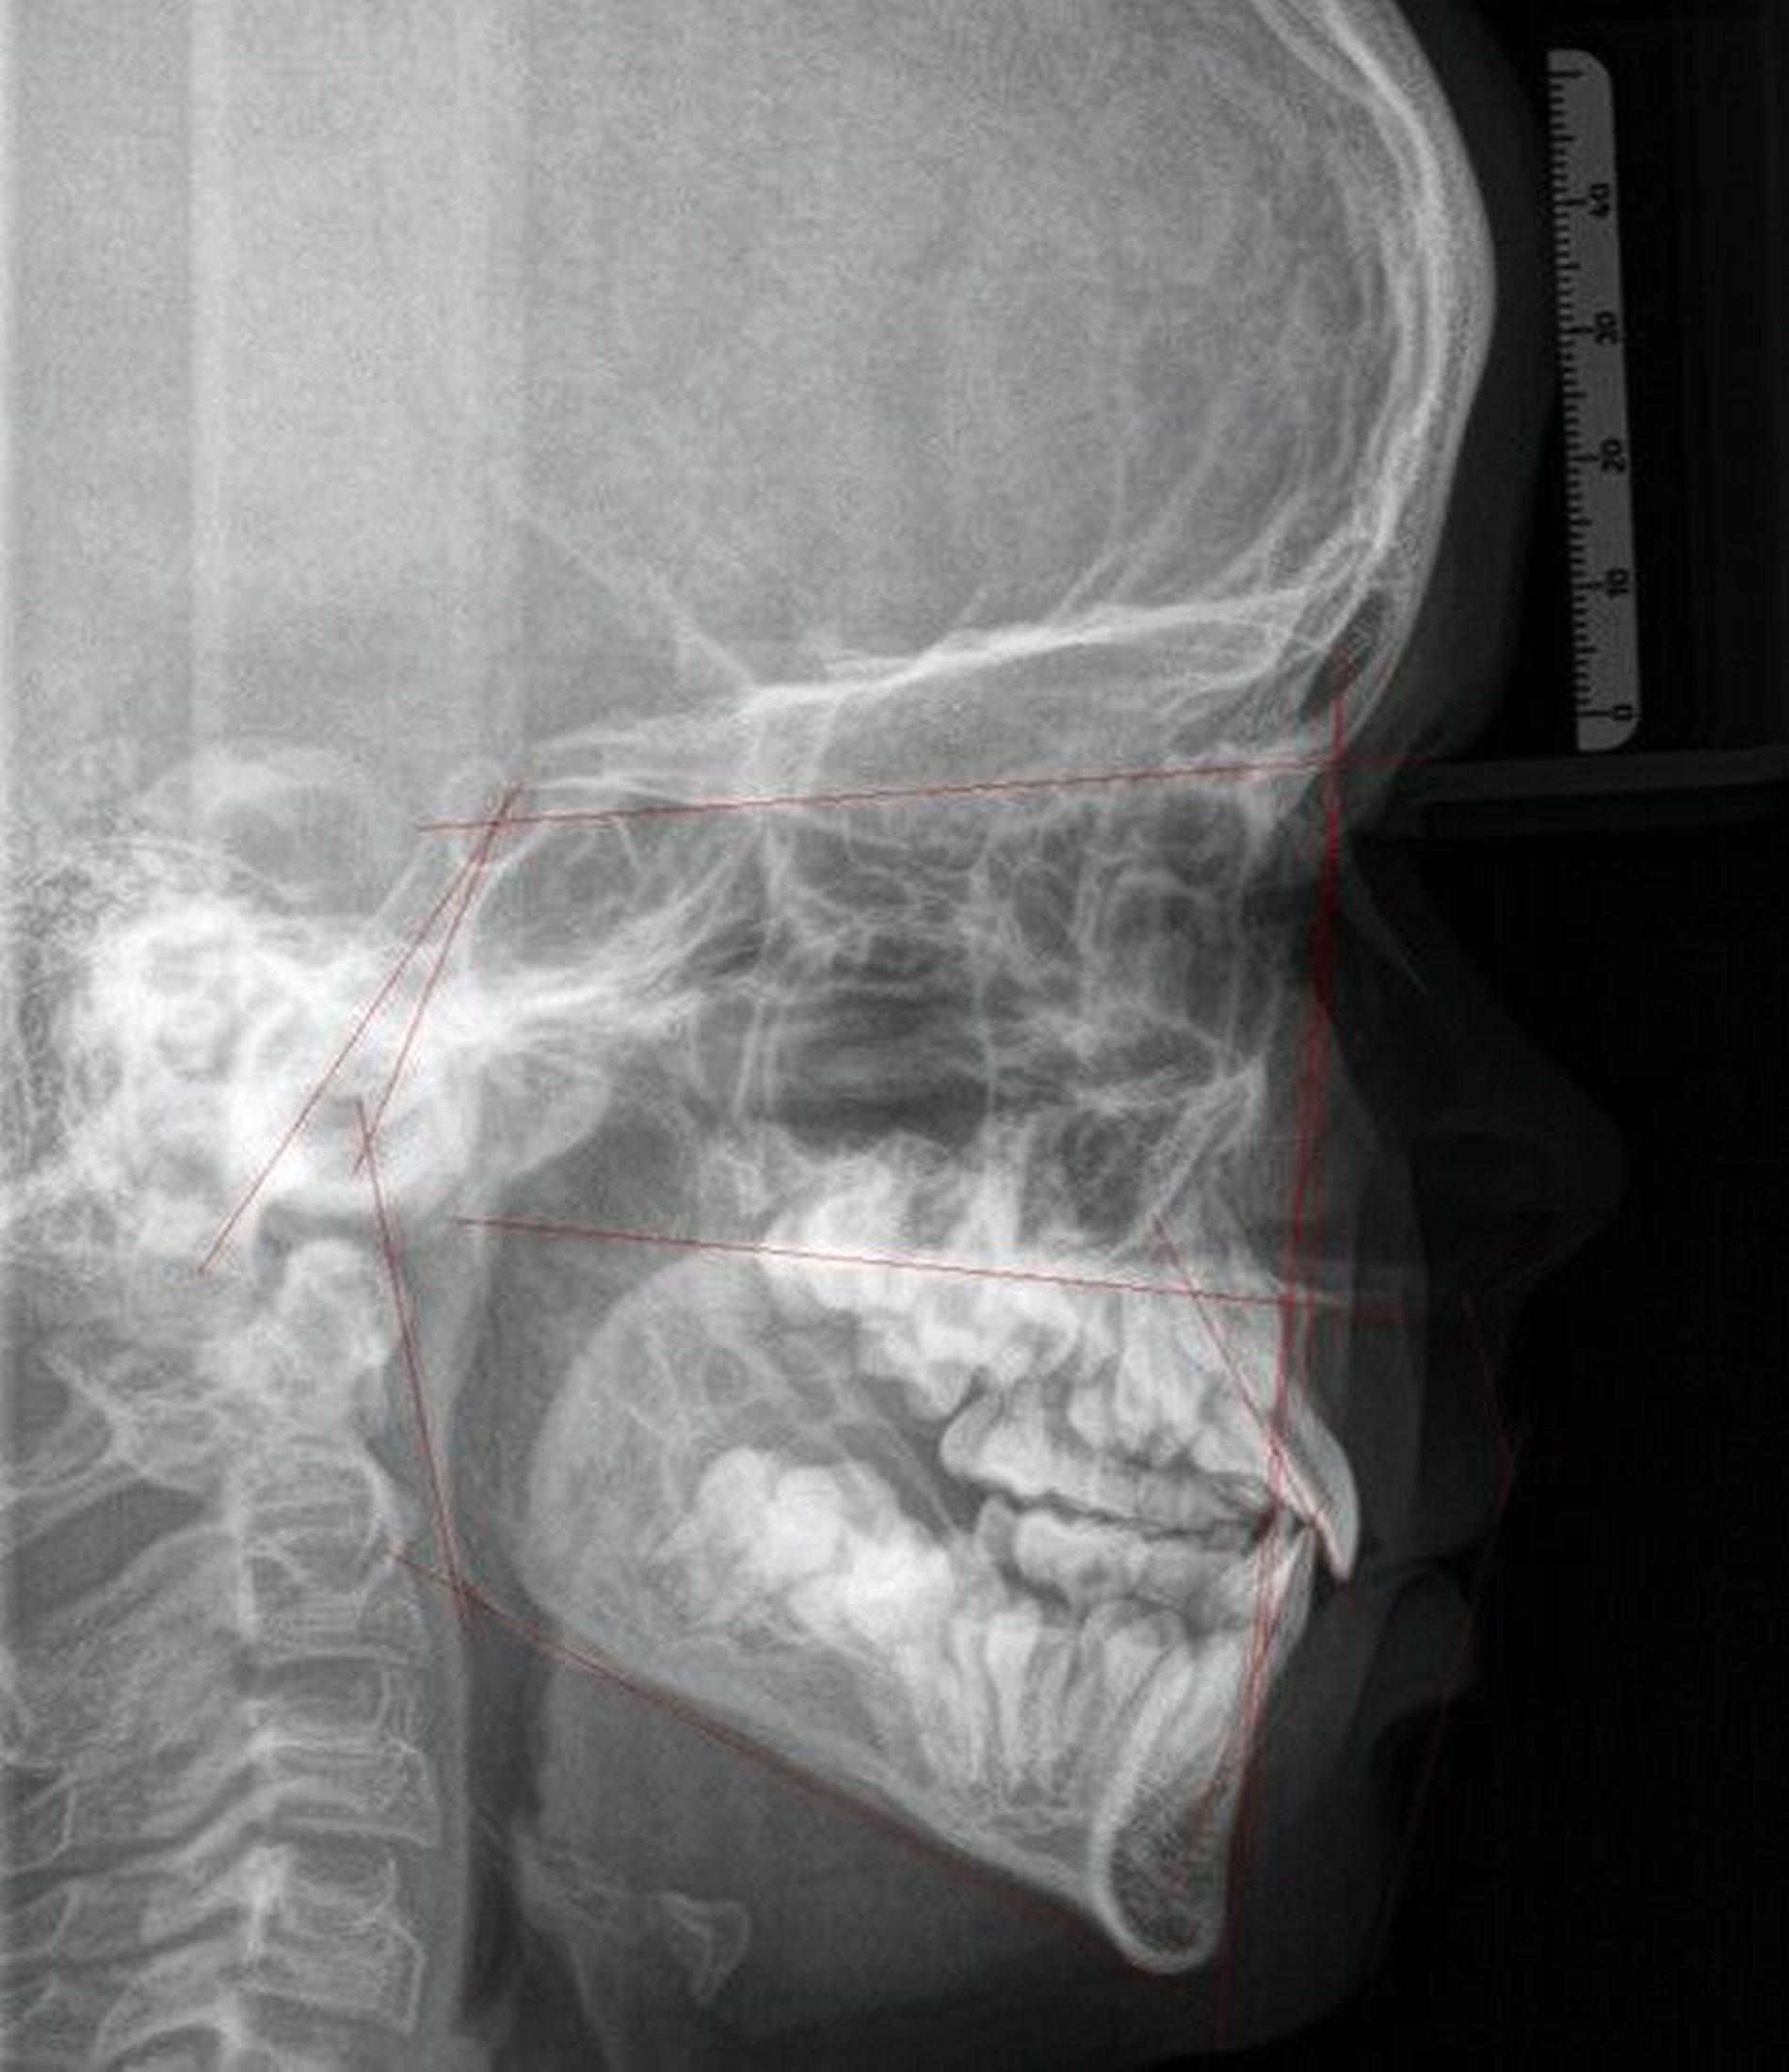

Ein zwölfjähriger Patient stellte sich in der Poliklinik für Kieferorthopädie des Universitätsklinikums Tübingen mit einer skelettalen Klasse-III-Konfiguration, einer Angle-Klasse III, einem Kreuzbiss auf der linken Seite und transversal schmalem Oberkiefer vor. Die Anamnese ergab ein vermindertes Hörvermögen, weshalb der Patient Hörgeräte trug. Darüber hinaus wurde keine Medikamenteneinnahme oder Allergie angegeben. Er wies mit einem dentalen Alter von sieben Jahren einen verzögerten Zahndurchbruch auf. Der initiale intraorale Befund zeigte die in situ befindlichen Zähne 11, 21 und 32–42. Die Zähne 12 und 22 eruptierten in Inklinationsfehlstellung. Die Milcheckzähne und -molaren befanden sich noch in situ. Die Sechsjahrmolaren waren nicht eruptiert und zeigten eine Verlagerungstendenz, insbesondere im Unterkiefer (Abbildung 1, Tabelle 1).

Die initiale Panoramaschichtaufnahme zeigte die Verlagerung mehrerer Zahnkeime sowie einen Platzmangel der Eckzähne und der Prämolaren im Oberkiefer (Abbildung 1b). Die Keimkrone von Zahn 13 wies dabei eine enge Lagebeziehung zum Zahnkeim 12 auf (Abbildung 1b). Die bereits eruptierten permanenten Frontzähne zeigten eine Angulations- und eine Inklinationsfehlstellung. Im distalen Bereich waren keine Durchbruchshindernisse erkennbar. Vor Beginn der kieferorthopädischen Behandlung wurde eine Primäre Zahndurchbruchsstörung (Primary Failure of Eruption – PFE) genetisch ausgeschlossen.

Bei der radiologischen Diagnostik bietet sich die DVT als Goldstandard für Patientinnen und Patienten mit multiplen verlagerten Zahnkeimen und verzögertem Zahndurchbruch an, da sie dem Kliniker ausreichende Informationen über die dreidimensionale Lokalisierung der Zahnkeime, potenziell überzählige Zähne, sensible Strukturen oder Wurzelresorptionen liefert [Hodges et al., 2013]. Dies ist entscheidend für eine präzise Diagnose, die eine fundierte Behandlungsplanung als Grundlage für eine erfolgreiche Therapie ermöglicht.

Im vorgestellten Beispiel wurde die DVT sowohl für die kieferorthopädische als auch für die chirurgische Behandlungsplanung verwendet. Daher ist die höhere Strahlenbelastung durch die DVT gegenüber einer Panoramaschichtaufnahme bei komplexen Patientenfällen gerechtfertigt und bietet einen maximalen Informationsgewinn. Darüber hinaus ermöglicht sie nicht nur eine prätherapeutische interdisziplinäre Diskussion über den Behandlungsplan, sondern auch eine exakte Planung für die Insertion von skelettalen Verankerungen [Bae et al., 2013; Qiu et al., 2012; Yu et al., 2012]. So war es möglich, die Lage der retinierten Zahnkeime zu bestimmen und sowohl die optimale Position als auch die Dimension der Mini-Implantate festzulegen.